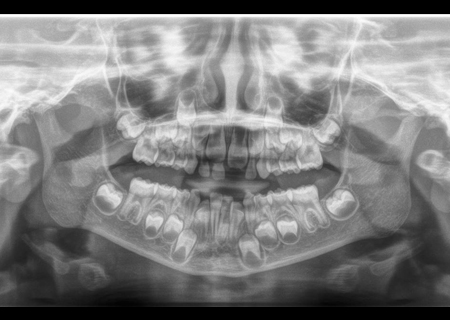

Ortopantomografía o Radiografía panorámica

La ortopantomografía , conocida también como OPT , es una radiografía extrabucal donde en una sola placa nos permite observar los maxilares superior e inferior y todos los dientes. La dosis de radiación es muy baja por ser un equipo digital. La Ortopantomografía (OPT) o radiografía panorámica, es un estudio radiológico que muestra desplegadas en un plano, las arcadas dentarias, sus tejidos de soporte y las estructuras anatómicas adyacentes. Es un estudio radiológico cómodo para el paciente, que se utiliza de forma rutinaria ya que permite apreciar todos los dientes y sus estructuras adyacentes en una sola imagen. Es una imagen bidimensional de un objeto tridimensional, y si es necesario un estudio tridimensional se puede completar con la tomografía volumétrica digital que además de abarcar los tres planos del espacio logran una definición de hasta 0,075 mm.

Se utiliza para:

- Evaluar dientes incluidos, no erupcionados

- Evaluar patrones de erupción, crecimiento y desarrollo dentario.

- Evaluación general del estado periodontal.

- Detectar manifestaciones de enfermedades sistémicas.

- Evaluación de lesiones extensas que sobrepasan las estructuras dentarias

- Evaluación de fracturas en los maxilares.